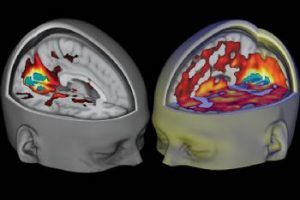

Suplementación con glutamina y alanina y marcadores de fatiga central

Recientes evidencias sugieren que el aumento en la síntesis de serotonina cerebral puede afectar negativamente al rendimiento en ejercicios intermitentes